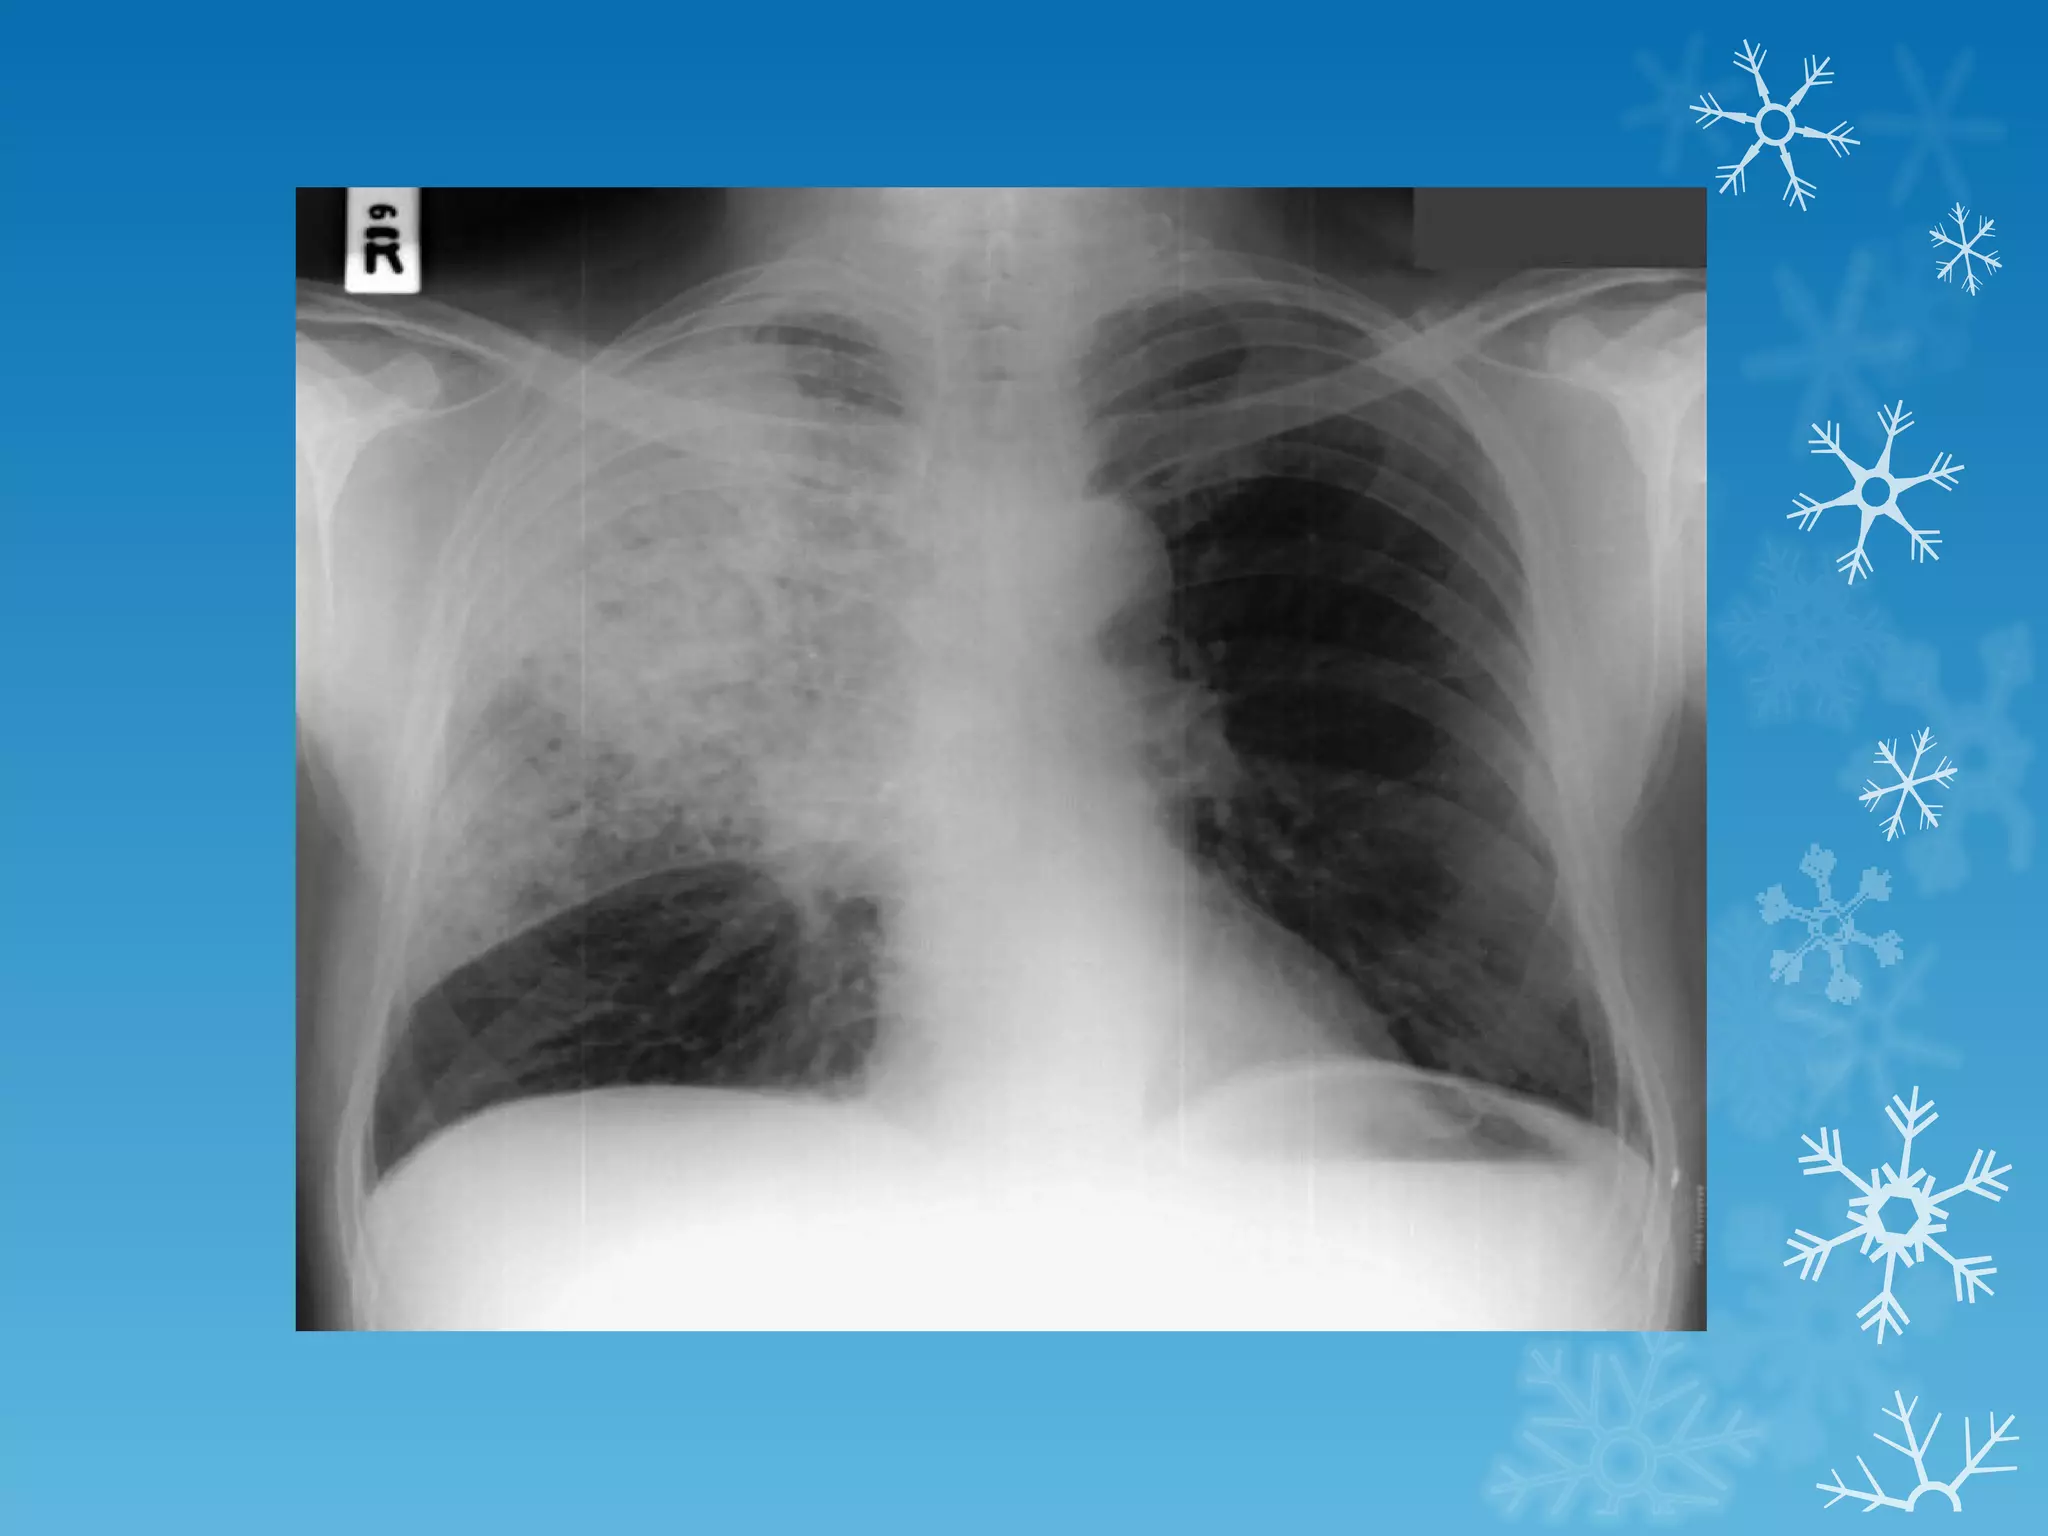

This document discusses chest x-ray interpretation and provides guidance on evaluating x-rays. It explains that tissue density determines how an x-ray beam penetrates, with denser tissues appearing whiter and less dense tissues appearing blacker. It also outlines different chest x-ray views and factors to consider like patient orientation, age, gender, and rotation. Abnormalities are described as appearing too white, too black, too large, or in the wrong place. The document stresses a systematic approach of identifying, localizing, describing lesions, and providing differential diagnoses.